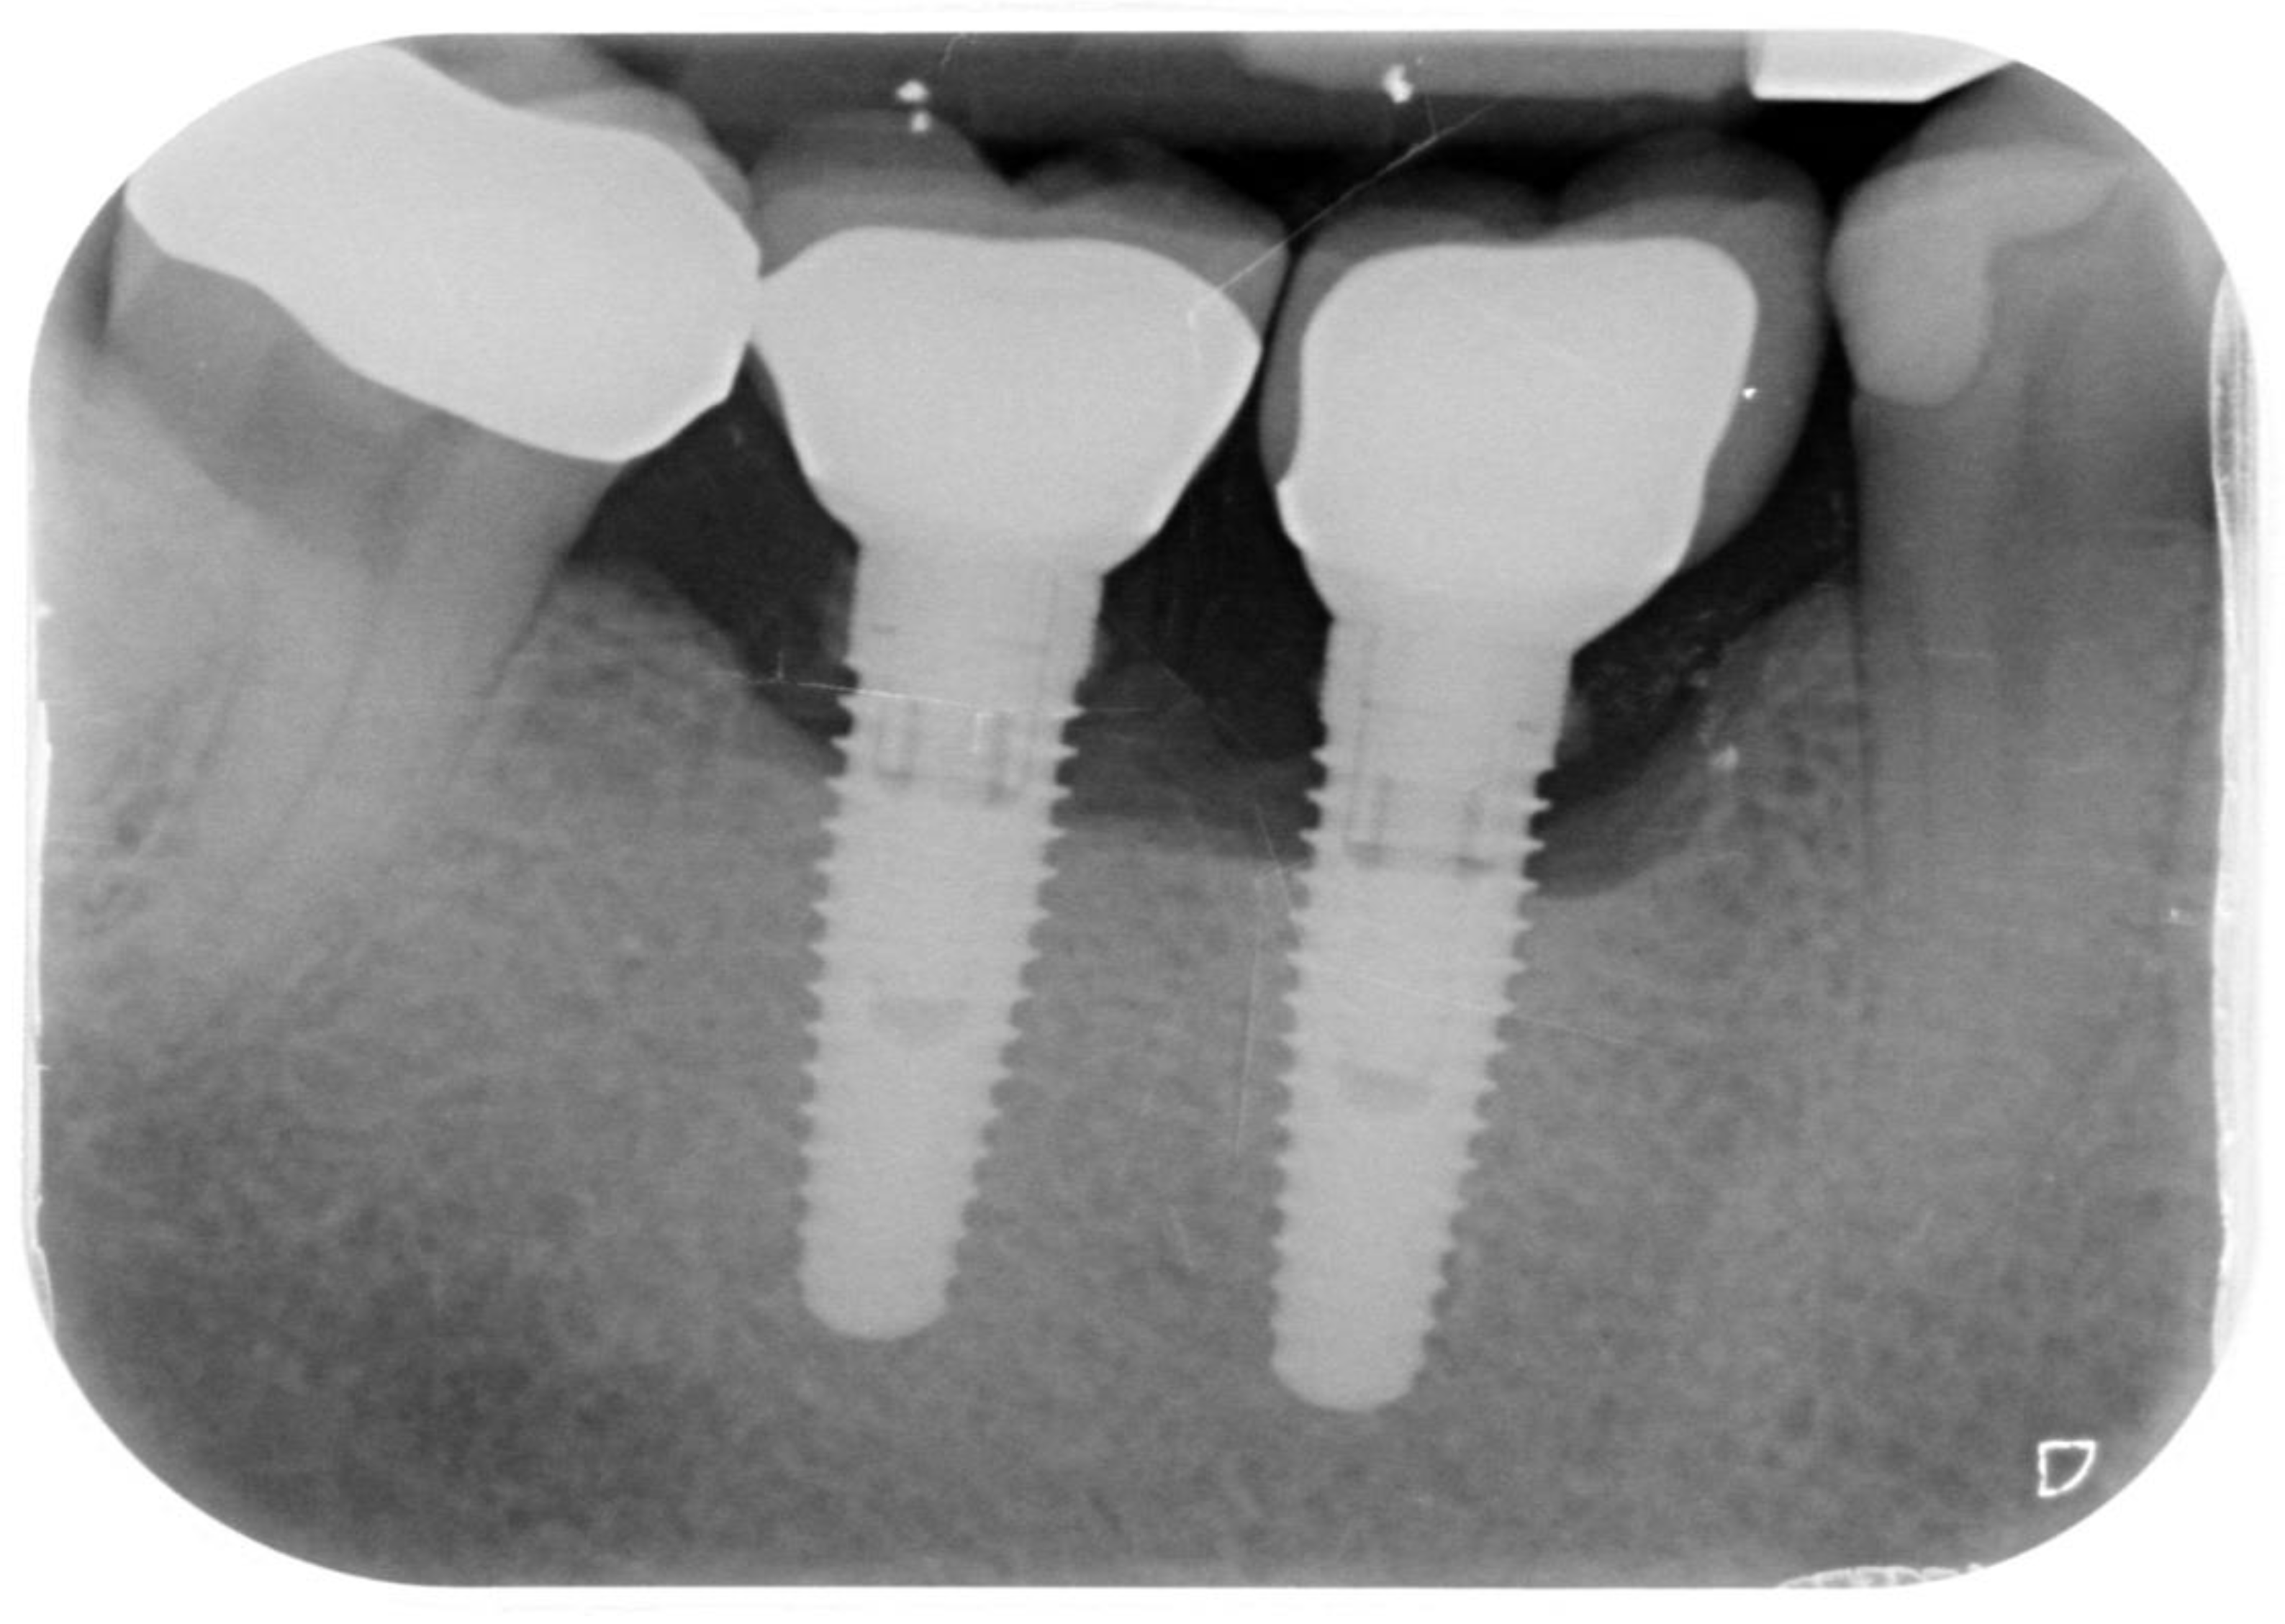

Peri-Implantitis: Application of a Protocol for the Regeneration of Deep Osseous Defects. A Retrospective Case Series

2. Materials and Methods